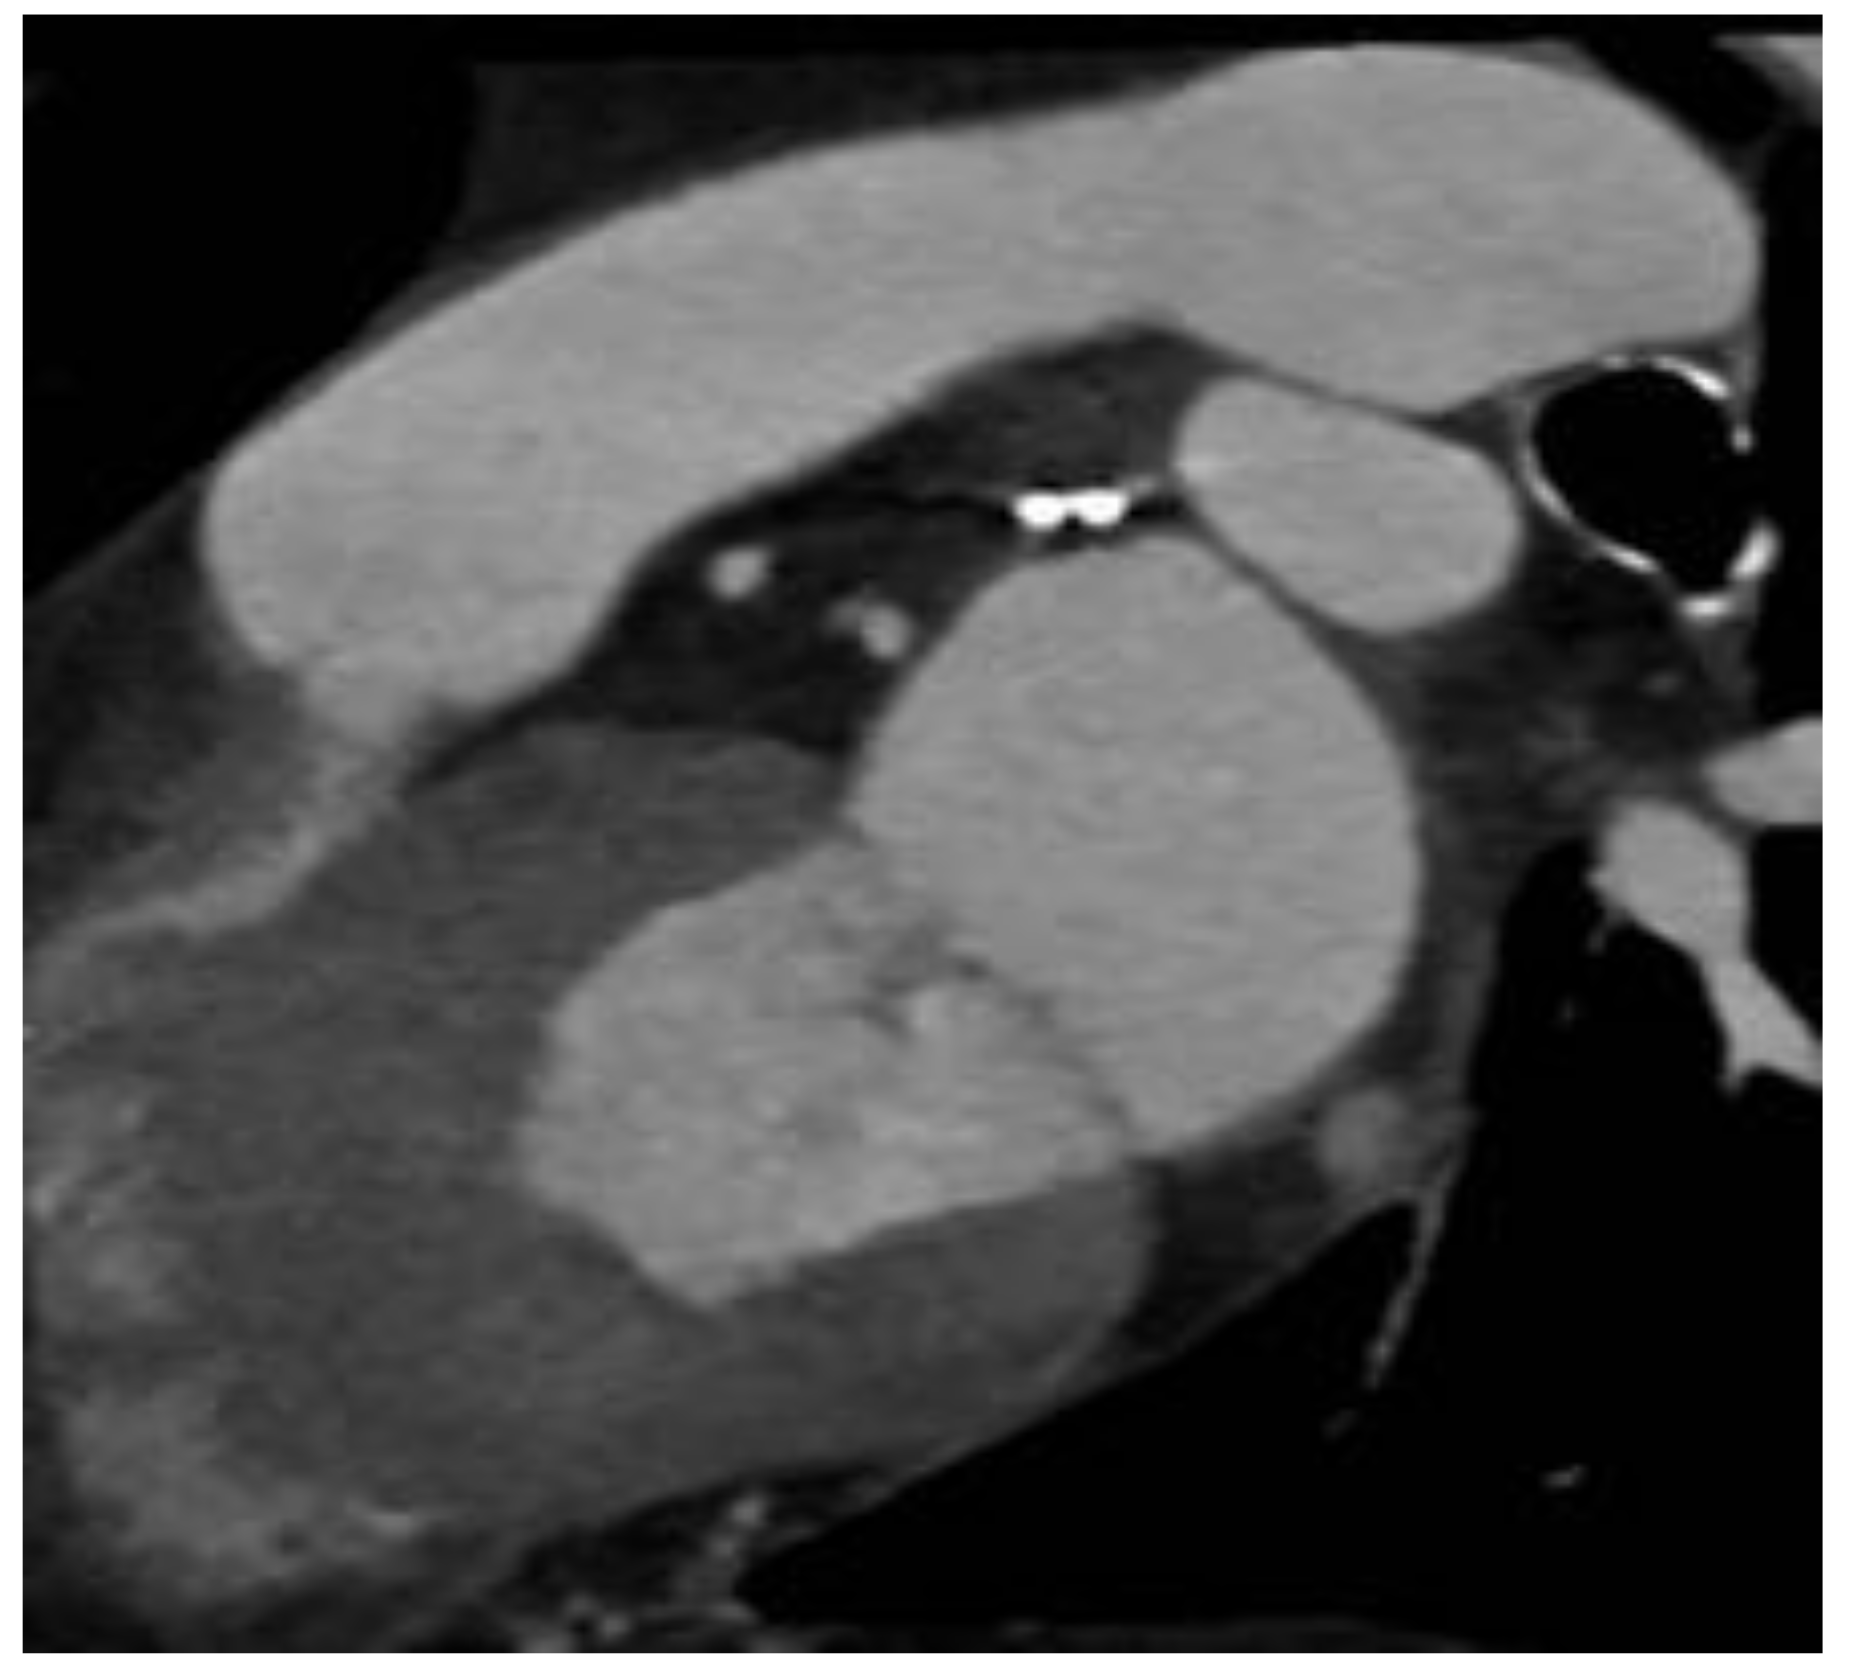

2.2. LAAO-T Procedure